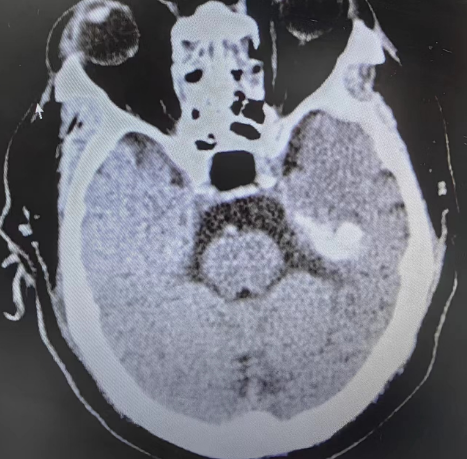

术前影像学检查

为挽救郭大爷的生命和视力,绵阳三医院神经外科决定为其进行经鼻手术切除。但由于郭大爷长期吸烟饮酒,还患有糖尿病及高血压,进一步增加了手术和麻醉风险。经我院副院长、神经外科专家刘阳与医疗团队讨论,决定在神经内镜的配合下切除肿瘤,这样既避免了对肿瘤周围结构的损伤,也能减少术中出血,加快肿瘤的切除速度。